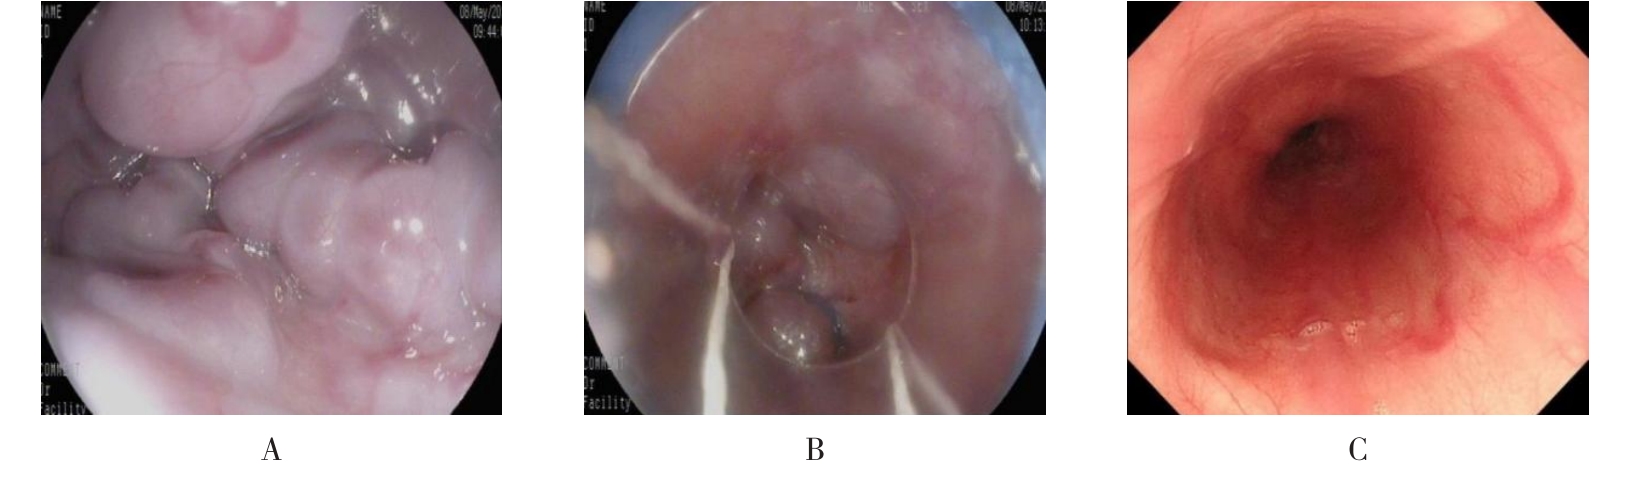

• 内镜序贯治疗儿童门静脉高压症伴食管胃静脉曲张破裂出血的疗效观察

2026, 32(3):51-57. DOI: 10.12235/E20250458

摘要 (30) HTML (26) PDF 2.07 M (31) 评论 (0) 收藏

摘要:目的 评估内镜序贯治疗儿童门静脉高压症(PHT)伴食管胃静脉曲张破裂出血(EVB)的临床疗效。方法 回顾性分析2010年6月-2023年2月于该院内镜下序贯治疗的PHT伴EVB的患儿21例。收集患儿病史特点、内镜表现、疗效和术后生长发育情况,分析所需内镜次数、术后即刻止血率、术后再出血率、术后并发症、生存率和术后长期生长发育情况。结果 患儿平均年龄(6.86±2.95)岁。末次治疗前血红蛋白水平明显高于首次入院,差异有统计学意义(P < 0.01)。共行81次(105项次)内镜下治疗,21例患者接受治疗次数的中位数为4.00(1.00,10.00)次。其中,18例患者接受内镜下套扎治疗,每例次套扎环数为7.0(6.00,12.00)环。内镜下硬化剂注射(EIS)治疗18例,每例次硬化剂用量为(12.29±5.67)mL。内镜下组织黏合剂注射治疗19例,每例次组织胶用量为(2.96±1.24)mL。内镜下即刻止血率为100.00%。6个月内再出血率为4.76%(1/21),6个月以上再出血率为14.28%(3/21)。至随访结束,4例患儿成年,体重指数(BMI)均在正常范围之内;其余17例未成年患儿年龄别体重Z评分(WAZ评分)明显改善(P < 0.01)。结论 内镜序贯治疗儿童PHT伴EVB安全、有效,促进患儿生长发育的同时,可作为外科手术后的补救措施,还可为未手术者提供手术或肝移植的机会。